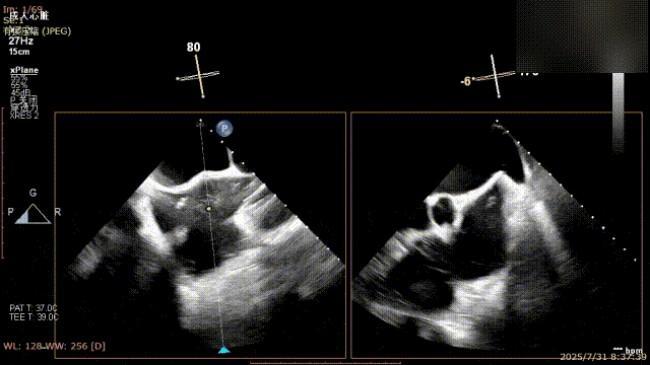

缓慢关闭夹合器

捕获瓣叶并放下Gripper

关闭夹合器